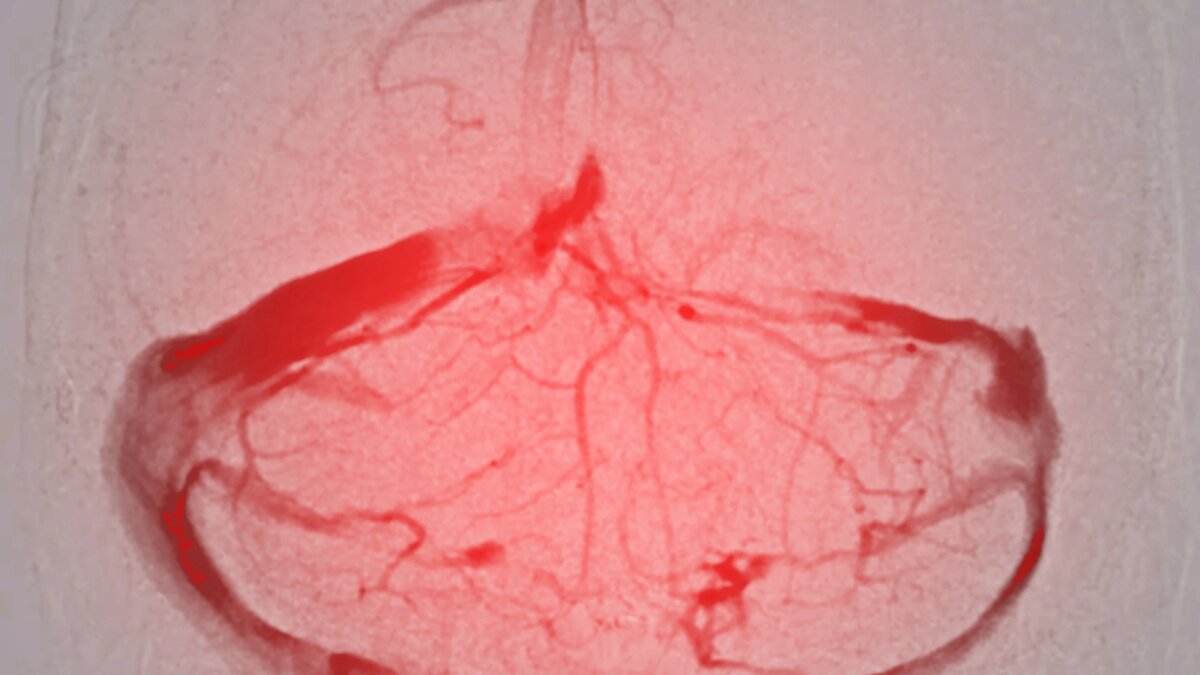

Для диагностики аневризмы аорты медики используют скрининговые методы, такие как рентгенография, которая может обнаружить косвенный признак заболевания. Также проводится эхокардиография, УЗИ сердца, компьютерная томография, магнитно-резонансная томографии, аортография (рентгенологическое исследование с введением контраста, который позволяет выявить патологию), рассказал Денис Прокофьев.